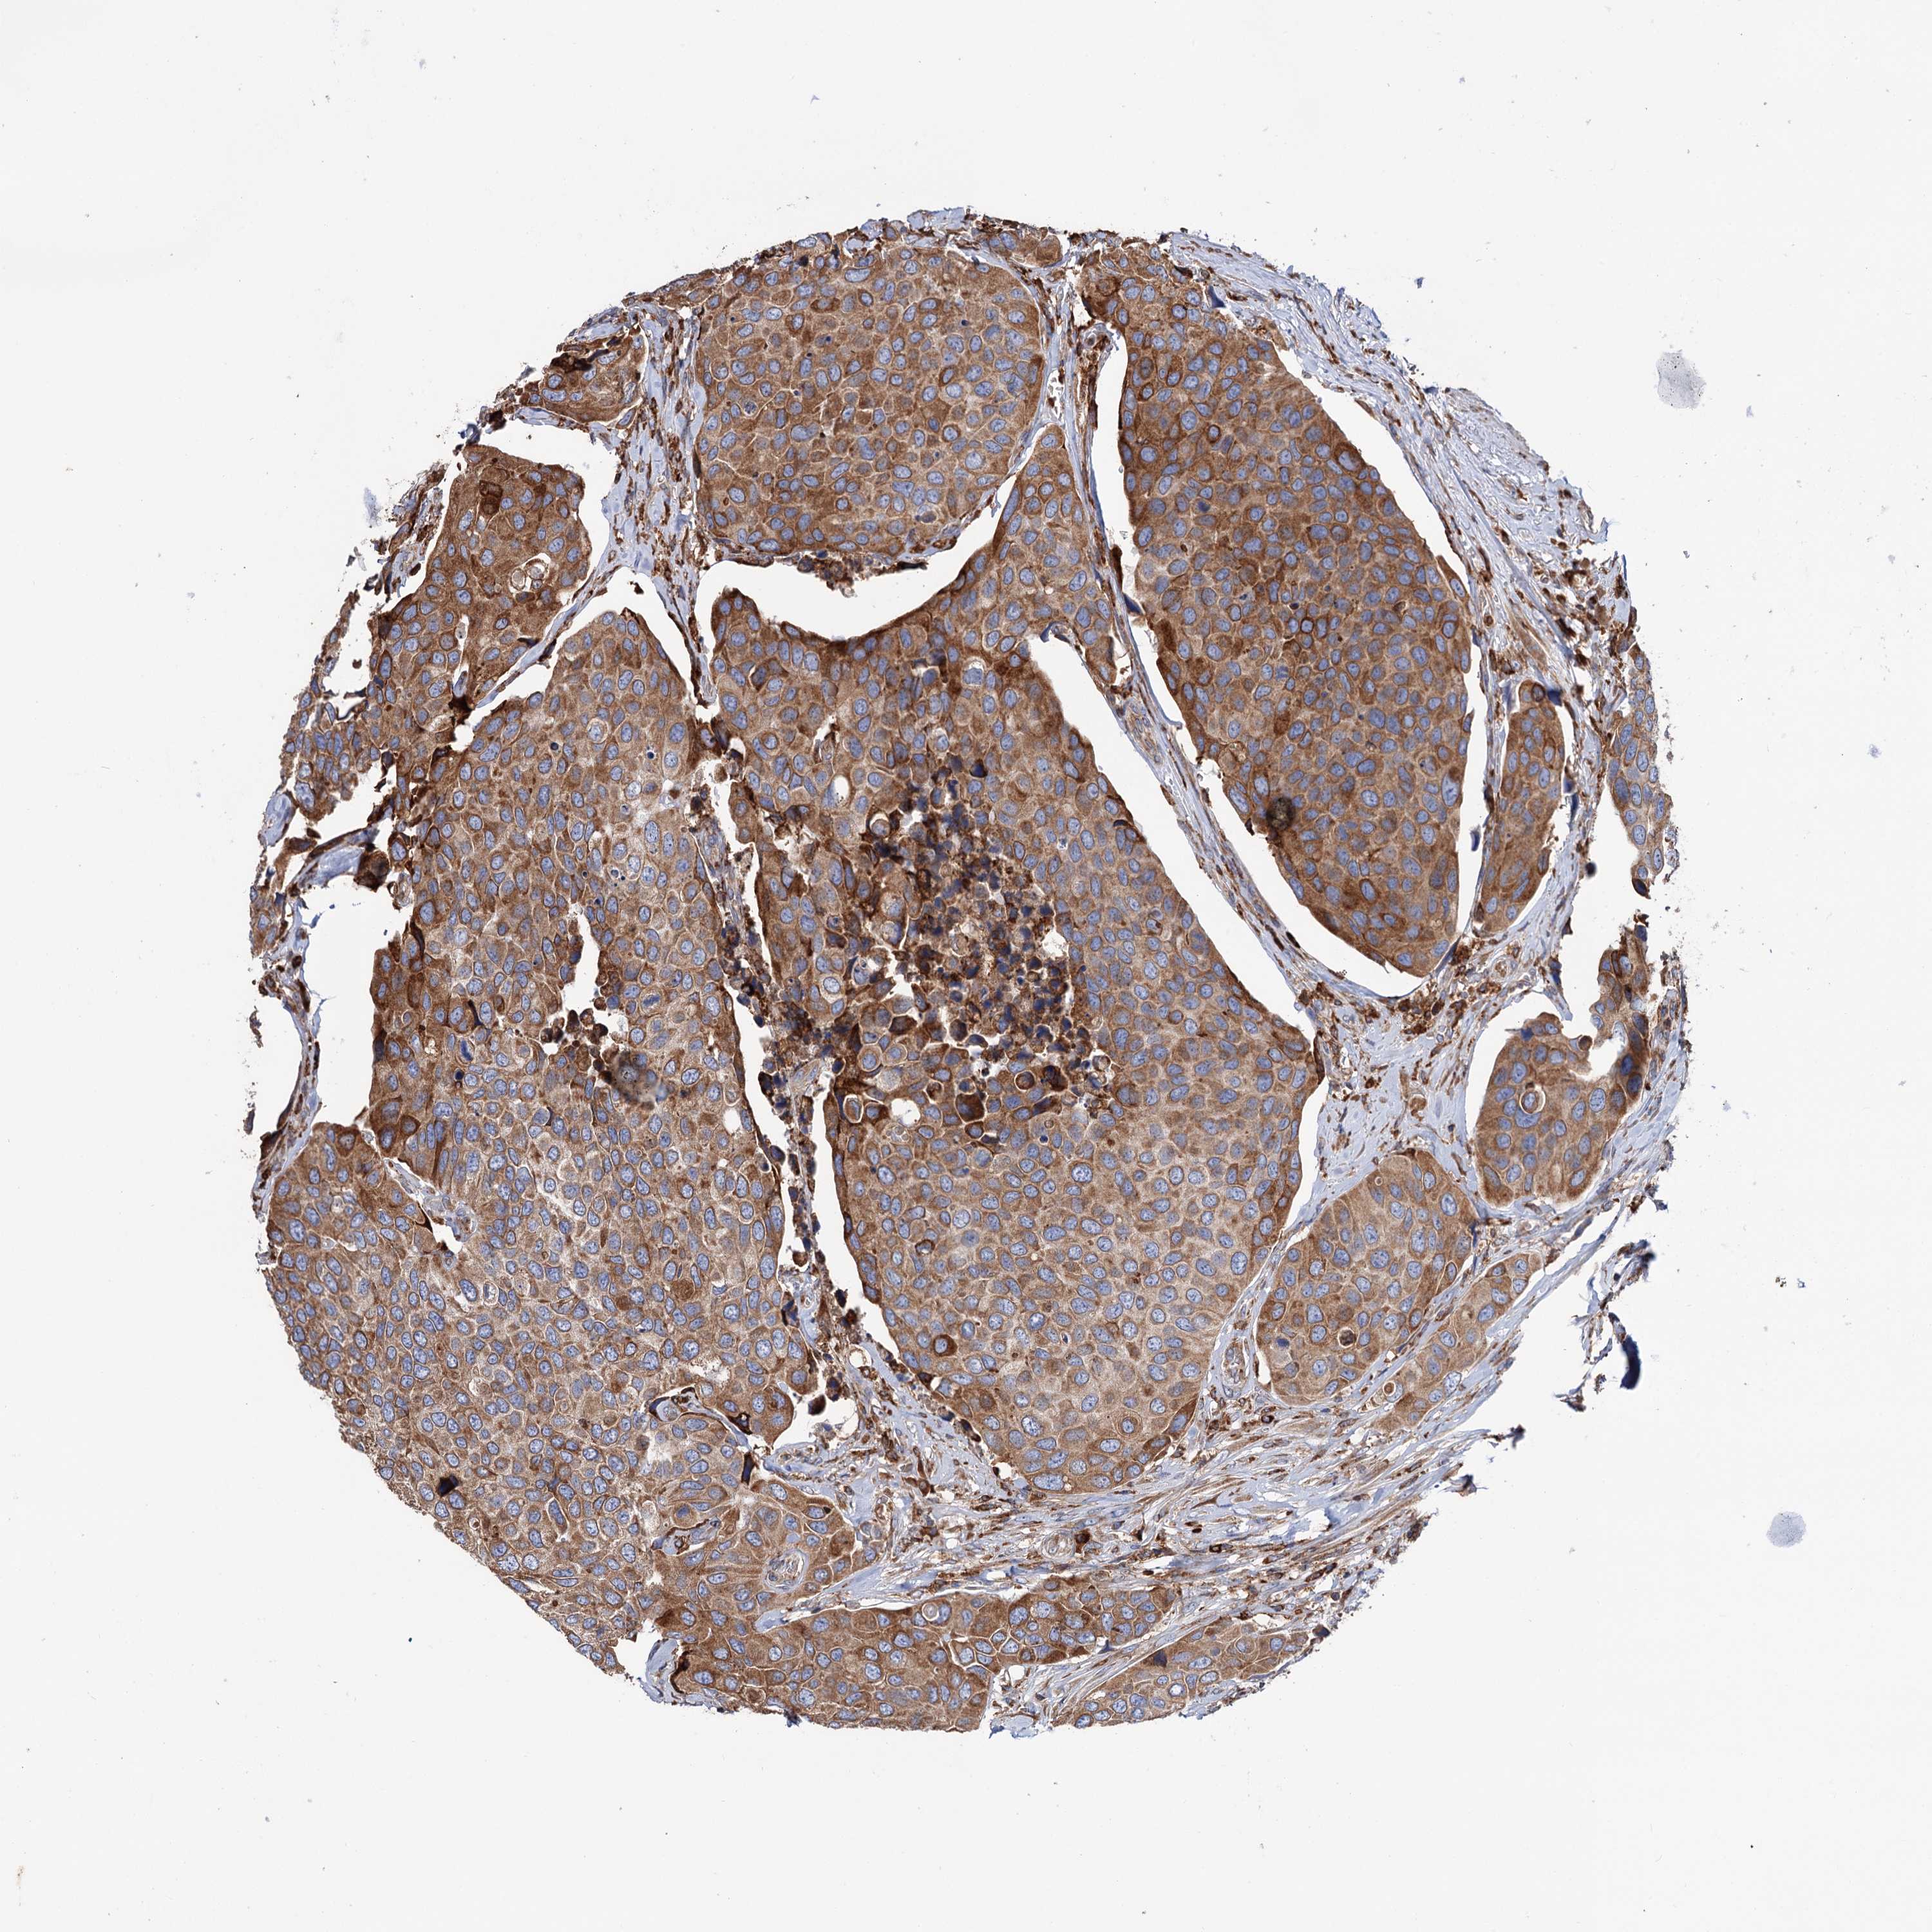

UROTHELIAL CANCER - Protein expressioni

A mouse-over function shows sample information and annotation data. Click on an image to view it in a full screen mode. Samples can be filtered based on level of antibody staining by selecting one or several of the following categories: high, medium, low and not detected. The assay and annotation is described here.

Note that samples used for immunohistochemistry by the Human Protein Atlas do not correspond to samples in the TCGA dataset.

Antibody stainingi

Antibody staining in the annotated cell types in the current human tissue is reported as not detected, low, medium, or high, based on conventional immunohistochemistry profiling in selected tissues. This score is based on the combination of the staining intensity and fraction of stained cells.

Each image is clickable and will lead to virtual microscopy that enables deeper exploration of all samples and also displays staining intensity scores, fraction scores and subcellular localization as well as patient and tissue information for each sample.

Antibody HPA039363

Antibody HPA039456

Staining

High

Medium

Low

Not detected

Intensity

Strong

Moderate

Weak

Negative

Quantity

>75%

75%-25%

<25%

None

Location

Nuclear

Cytoplasmic/membranous

Cytoplasmic/membranous,nuclear

Urothelial carcinoma, High grade